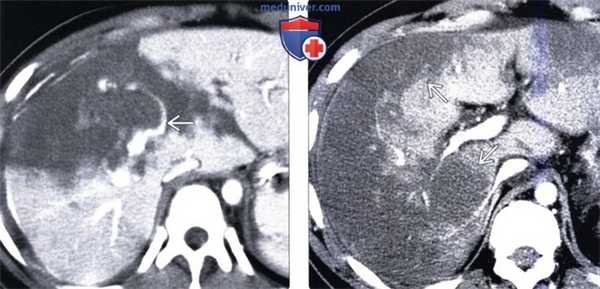

(Слева) На аксиальной КТ с контрастным усилением у пациента с тупой травмой живота определяется отсутствие контрастного усиления передних сегментов правой доли печени. Ветвь печеночной артерии, подходящая к этому сегменту, пересечена; определяется острая экстравазация контраста.

(Справа) На аксиальной КТ с контрастным усилением у мужчины 72 лет, которому была выполнена операция на сердце, и сразу же после выхода из наркоза возникла сильная боль в правом подреберье и нарушение функции печени, визуализируются обширные гиподенсные участки, не накопившие контраст, во всех отделах печени. Вскоре после завершения исследования пациент скончался.

(Слева) На аксиальной КТ с контрастным усилением у мужчины 57 лет, выполненной через неделю после холецистэктомии, определяется инфаркт печени, обусловленный повреждением артерии во время операции. Обратите внимание на «географический» гиподенсный участок и левой доле печени, хорошо отграниченный от окружающих тканей.

(Справа) На более каудальном КТ срезе у этого же пациента визуализируются клипсы в области левой долевой ветви печеночной артерии; видны также «пятнистые» гиподенсные участки в правой доле печени.